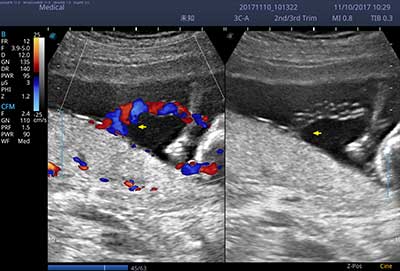

E3便携式彩色多普勒超声诊断系统拥有专业超声技术平台、高度集成化的硬件模块和结构设计、简便的操作流程、支持三探头接口全激活,兼顾了优质图像、轻便机身以及台便两用的临床使用需求。无论在常规超声科门诊检查,还是在急诊、麻醉、ICU、户外等各种应用场景。都能给您带来流程的操作体验。

一键自动优化